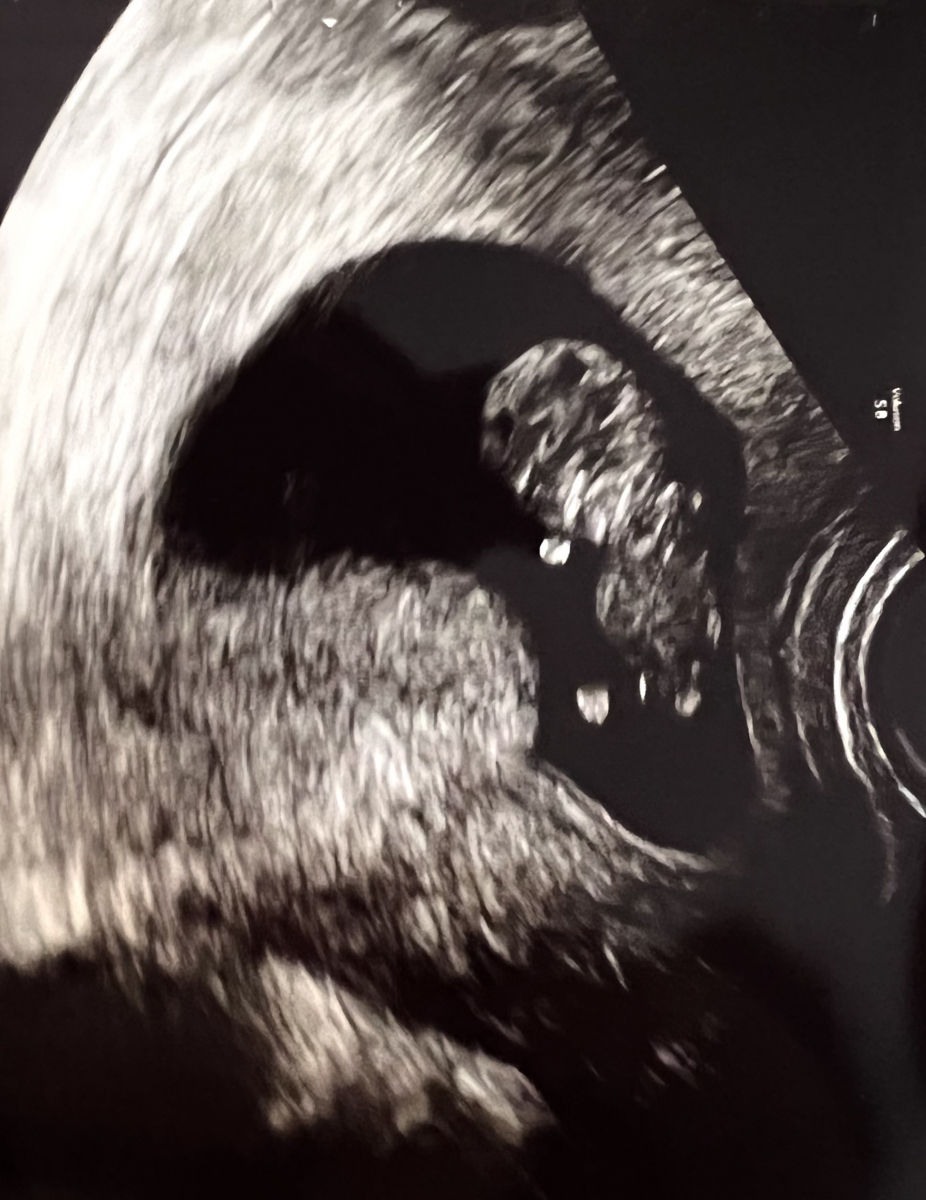

We had our first ultrasound at 8 weeks. The baby was a healthy blobby shrimp and it was surreal to see it inside of me. Our 10-week ultrasound was cuter, the baby looked like a gummy bear dancing with little stubby arms and legs. And our 12-week looked more human-like.